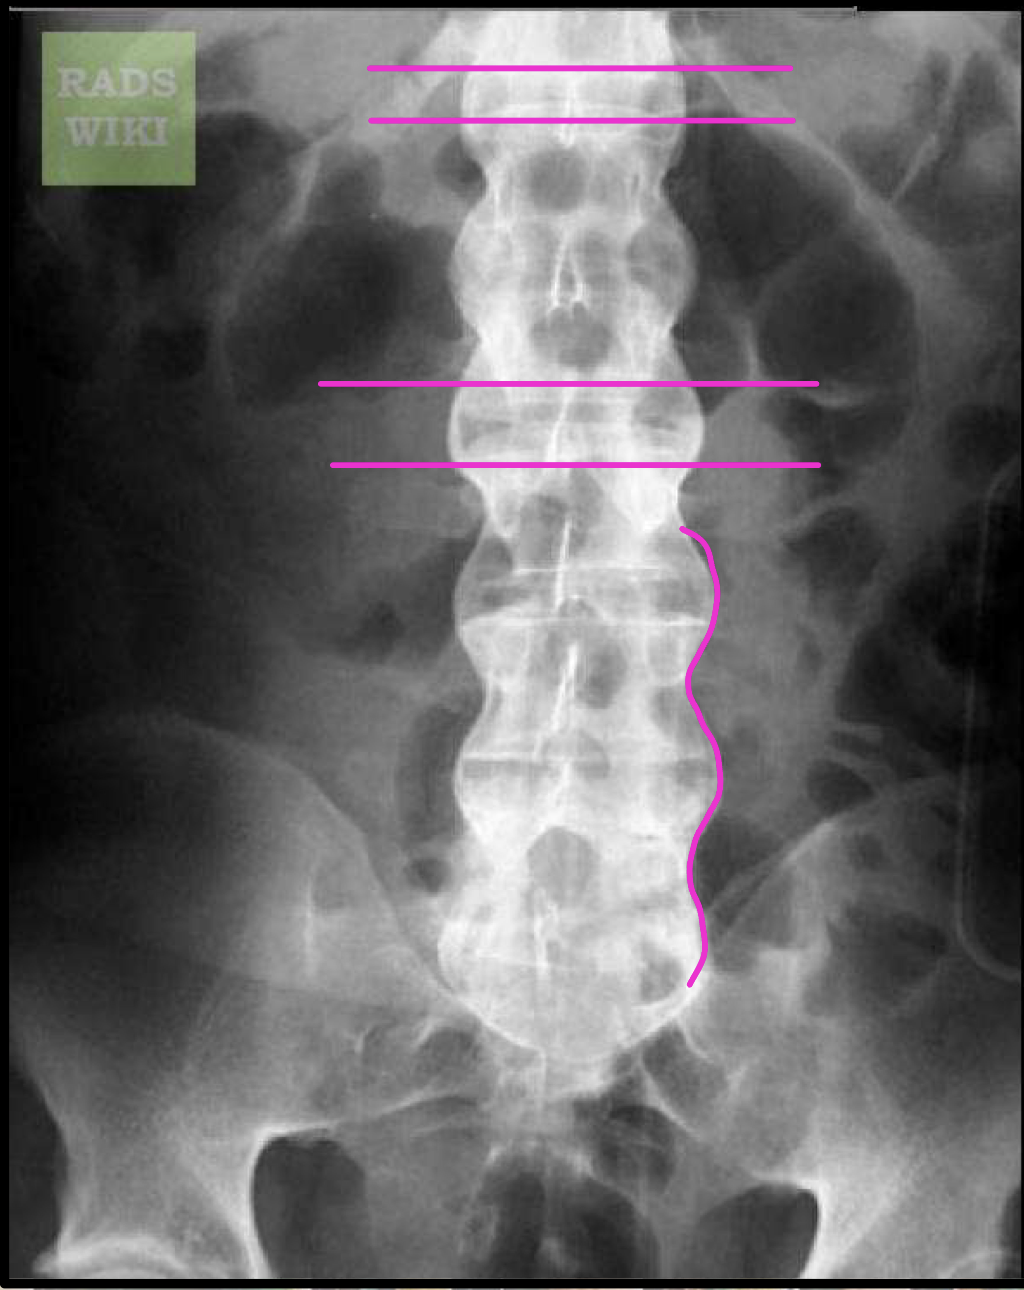

What finding of AS is found in this image

symmetrical, thin, marginal syndesmophytes (bamboo sign)

gracile/fragile

Interspinous ligament ossification (Dagger sign)

Z-joint/facet capsular ossification (Railroad track sign)

Dagger sign + Railroad track sign =

Trolley track sign